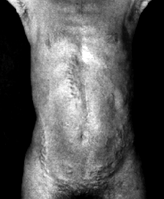

6.7.1 Diverticoli

del colon

La seguente radiografia a contrasto

mostra un esempio.